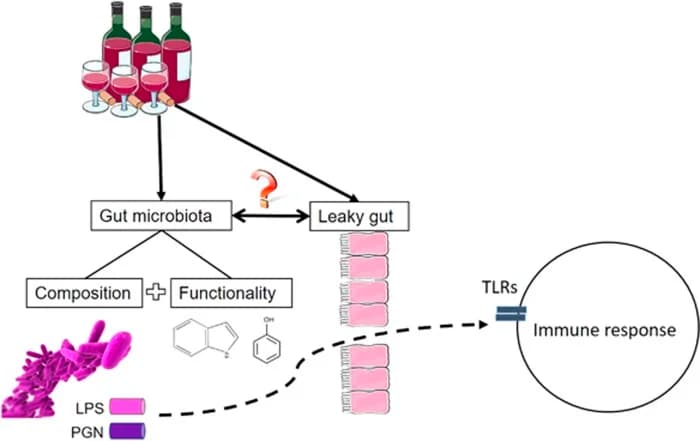

- Lowers inflammation and permeability in the gut. R R

CBD may relieve anhedonia and depression by its activity on Lipopolysaccharides (LPS).

7. Has Anti-Inflammatory Properties

CB2 receptors are expressed in several types of inflammatory cells and immunocompetent cells. R

Activating CB2 receptors inhibit the release of proinflammatory factors. R